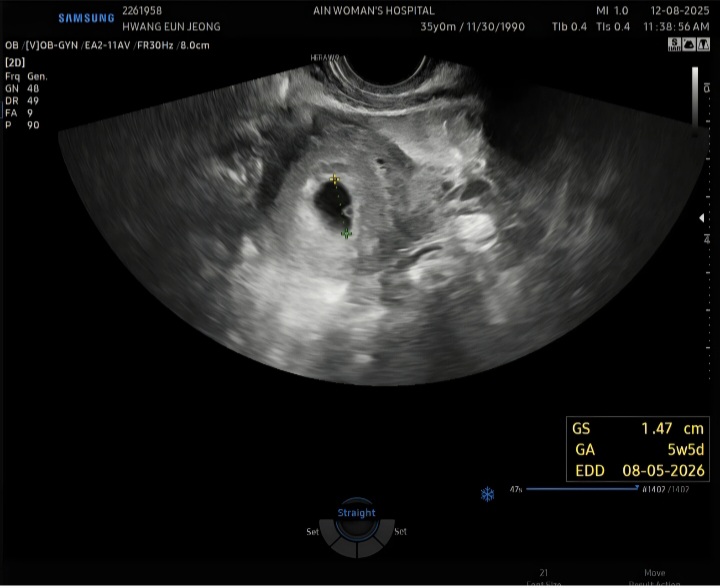

12월 8일 초음파 보고 왔어요~~

12월8일에 초음파 보고 왔어요 막생 기준 5주5일 이었고 2주후에 초음파 다시 보고 예정일 변경될수도 있다고 했거든요~ 2주가 왜이렇게 안가는지 ㅜㅜ 배동이나 맘카페 보면 입덧 심하신분들 많던데 전 입덧도 없고 가슴만 조금 아프고 피곤하기만해서 잘크고 있는건지 걱정이에요 초기에는 유산도 많다는데 ㅜㅜ 아직 심장소리 못들어서 괜히 걱정되네요 24일에 병원 예약이긴한데 그전에라도 동네병원 가보는게 나을까요? 그냥 좀 기다려볼까요...?